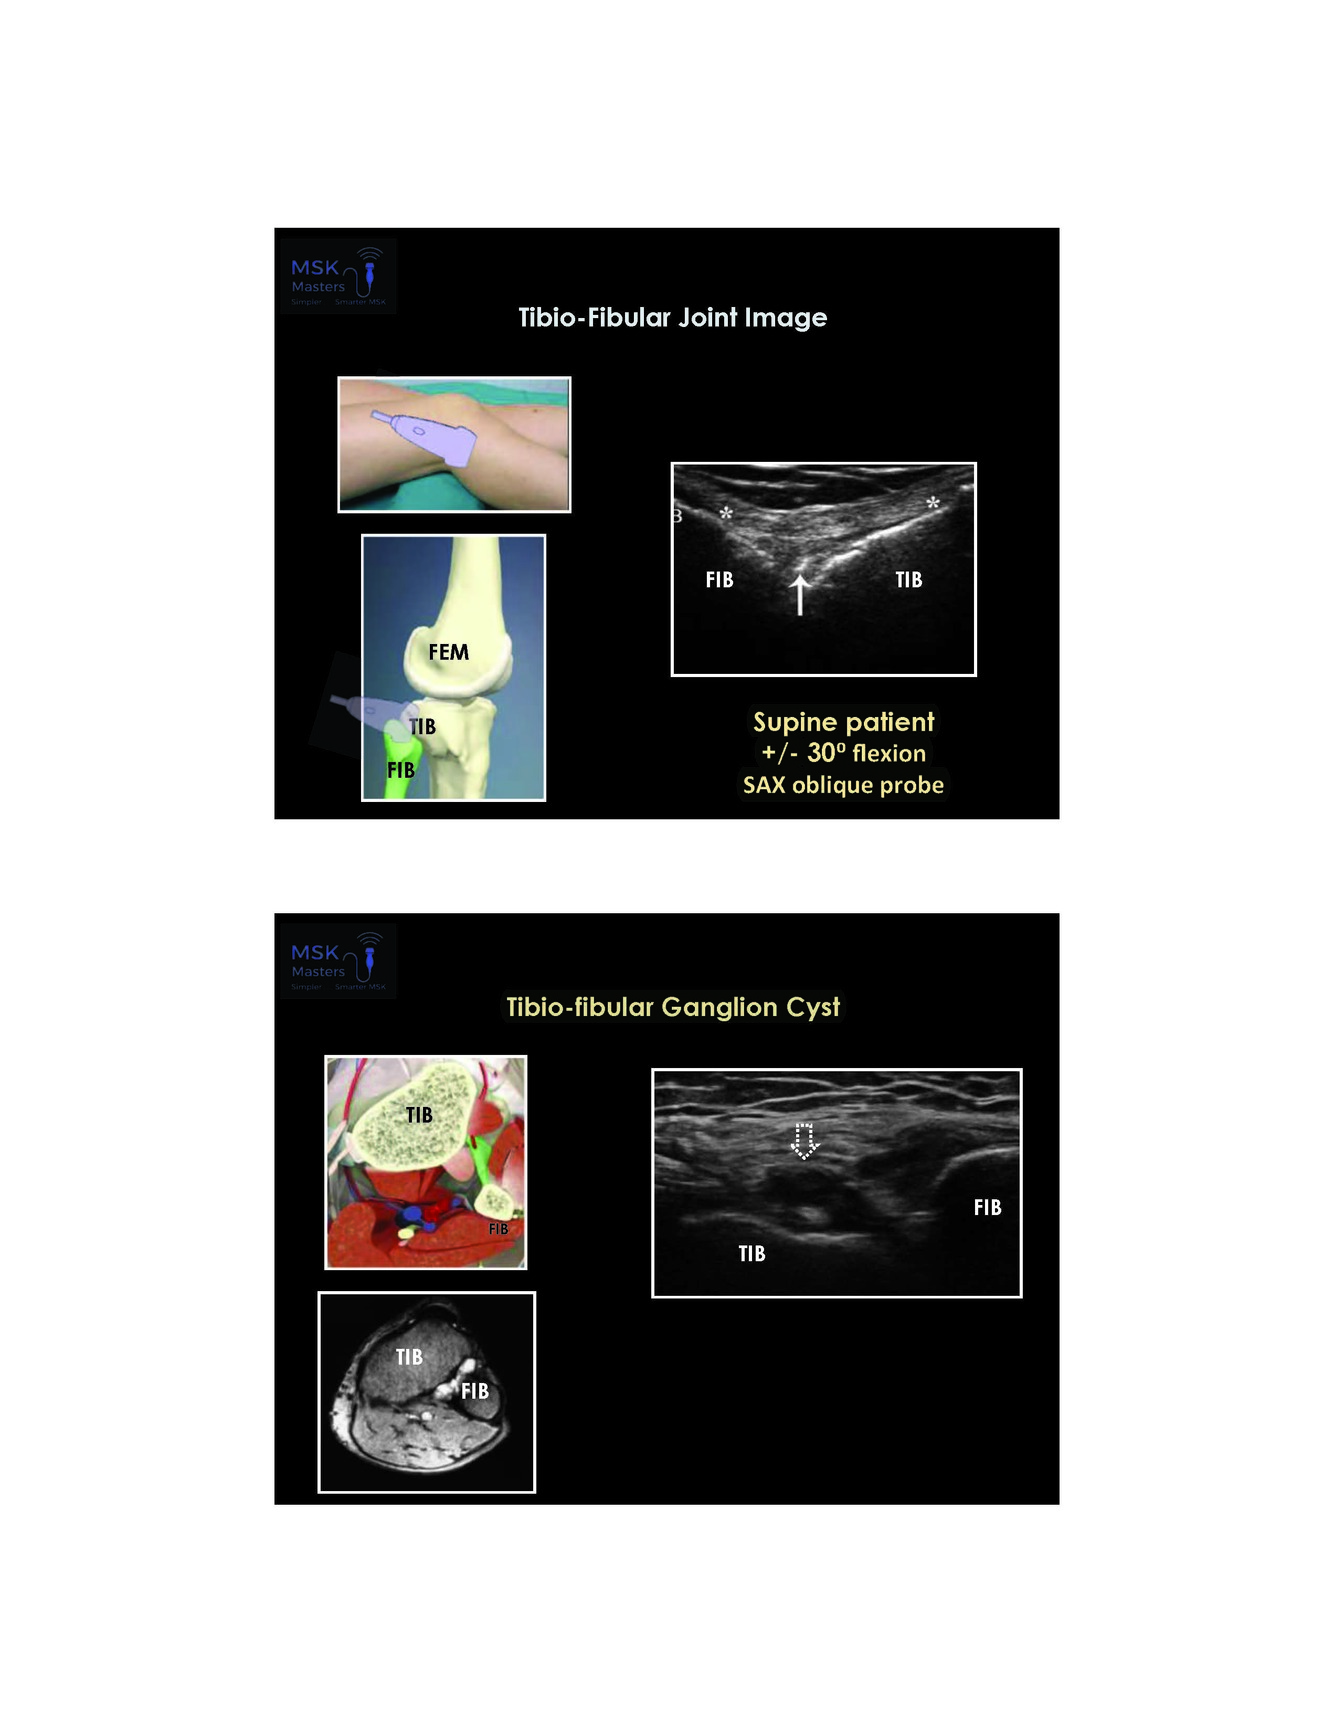

Image of tibio fibular joint

dont forget to take a look at this when people have lateral knee pain